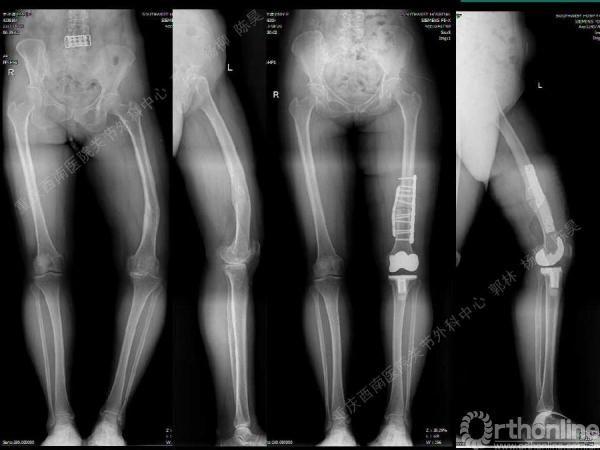

导读:文中,来自重庆西南医院的郭林教授为大家介绍了股骨冠状位关节外畸形的TKA的相关知识,并详细阐述了关节外畸形的概念、诊断、关节内滑移截骨技术等相关内容。